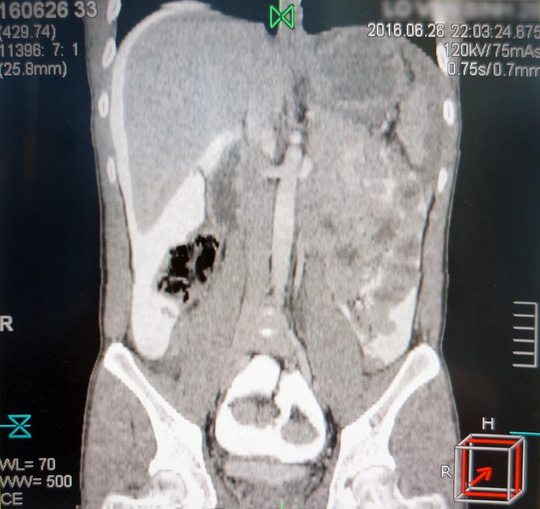

Ngày 3-7, Bệnh viện Xuyên Á (huyện Củ Chi-TP HCM) cho biết nơi đây vừa tiếp nhận cấp cứu một trường hợp vỡ bàng quang mà không hề hay biết. Bệnh nhân là anh L.V.S. (26 tuổi, ngụ huyện Hóc Môn). Trước đó, bệnh nhân nhập viện cấp cứu trong tình trạng vật vã, đau bụng dữ dội. Các kết quả cận lâm sàng, CT cho thấy anh S. bị vỡ bàng quang vết rách 12 cm trong phúc mạc. Các bác sĩ chuyên Khoa Cấp cứu, Ngoại Tiết niệu phẫu thuật cấp cứu khâu lại bàng quang cứu bệnh nhân. Hiện bệnh nhân qua nguy kịch, sức khỏe tạm ổn định.